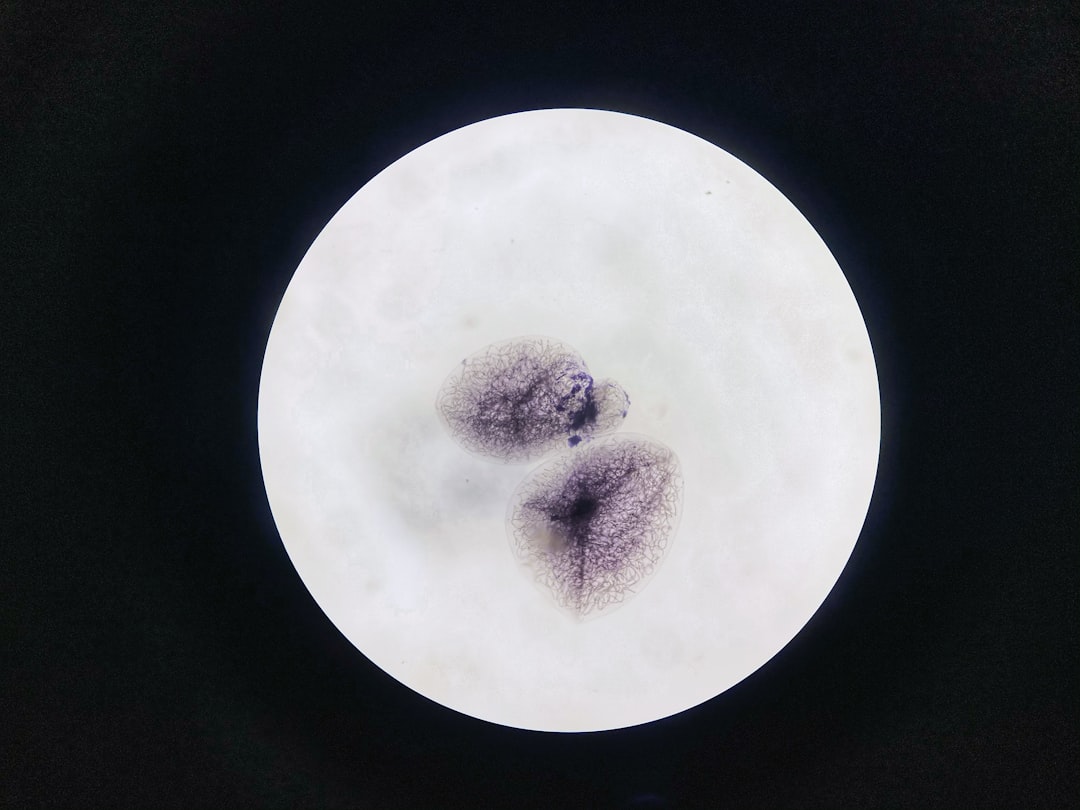

Pe parcursul examinării, medicul va căuta anomalii precum polipi, inflamații sau leziuni. Dacă se identifică polipi sau alte anomalii, medicul poate decide să efectueze o biopsie sau să îndepărteze polipii pe loc. Biopsiile sunt trimise ulterior la laborator pentru analize suplimentare.